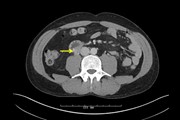

Abdominal pain and hematuria: duodenal perforation from ingested foreign body causing ureteral obstruction and hydronephrosis

Nina Kolbe and others

Journal of Surgical Case Reports, Volume 2016, Issue 2, February 2016, rjw018, https://doi.org/10.1093/jscr/rjw018